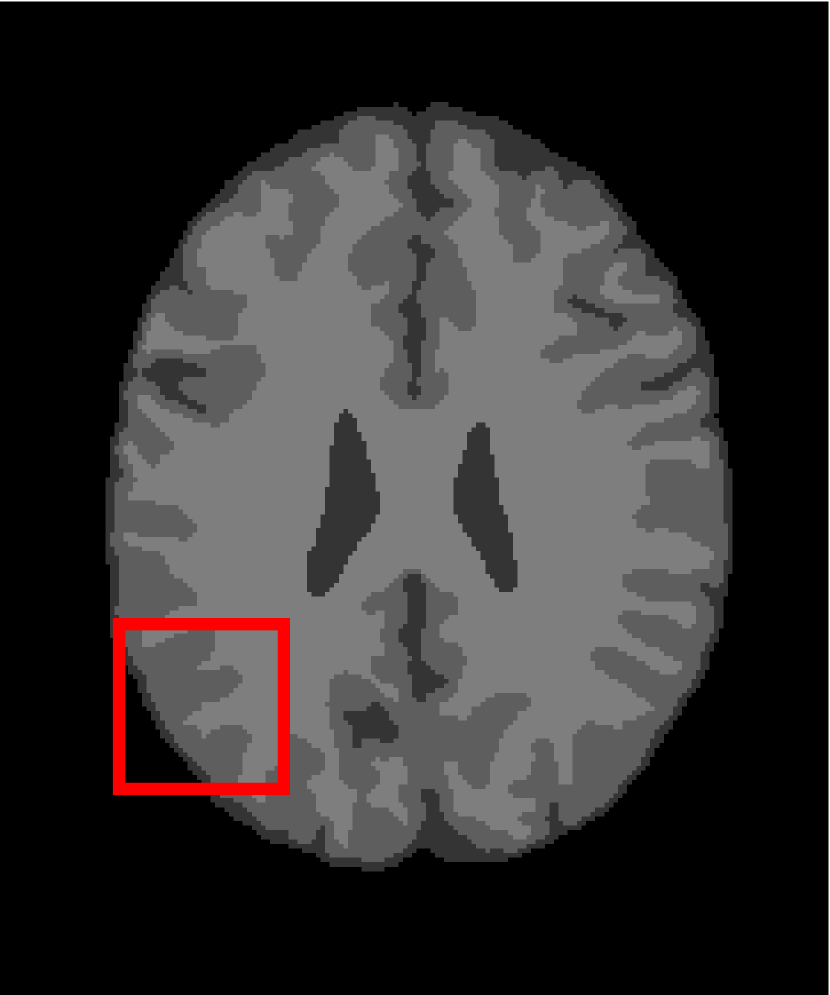

Next, we representatively segment five medical images from BrianWeb. They are represented as five slices in the axial plane with a sequence of 70, 80, 90, 100 and 110, which are generated by T1 modality with slice thickness of 1mm resolution, 9% noise and 20% intensity non-uniformity. Here, we set c=4𝑐4c=4 for all cases. The comparison between WRFCM and its peers are shown in Fig. 9 and Table II. The best values are in bold.

Figure 9: Segmentation results on five medical images. The parameter: ϕ=5.35italic-ϕ5.35\phi=5.35. From top to bottom: noisy images, ground truth, and results of FCM_S1, FCM_S2, FLICM, KWFLICM, FRFCM, WFCM, DSFCM_N, and WRFCM.

By a view of the marked red square in Fig. 9, we find that FCM_S1, FCM_S2, FLICM, KWFLICM and DSFCM_N are vulnerable to noise and intensity non-uniformity. They give rise to the change of topological shapes to some extent. Unlike them, FRFCM and WFCM achieve sufficient noise removal. However, they produce overly smooth contours. Compared with its seven peers, WRFCM can not only suppress noise adequately but also acquire accurate contours. Moreover, it yields the visual result closer to ground truth than its peers. As Table II shows, WRFCM obtains optimal SA, SDS and MCC results for all five medical images. As a conclusion, it outperforms its peers visually and quantitatively.